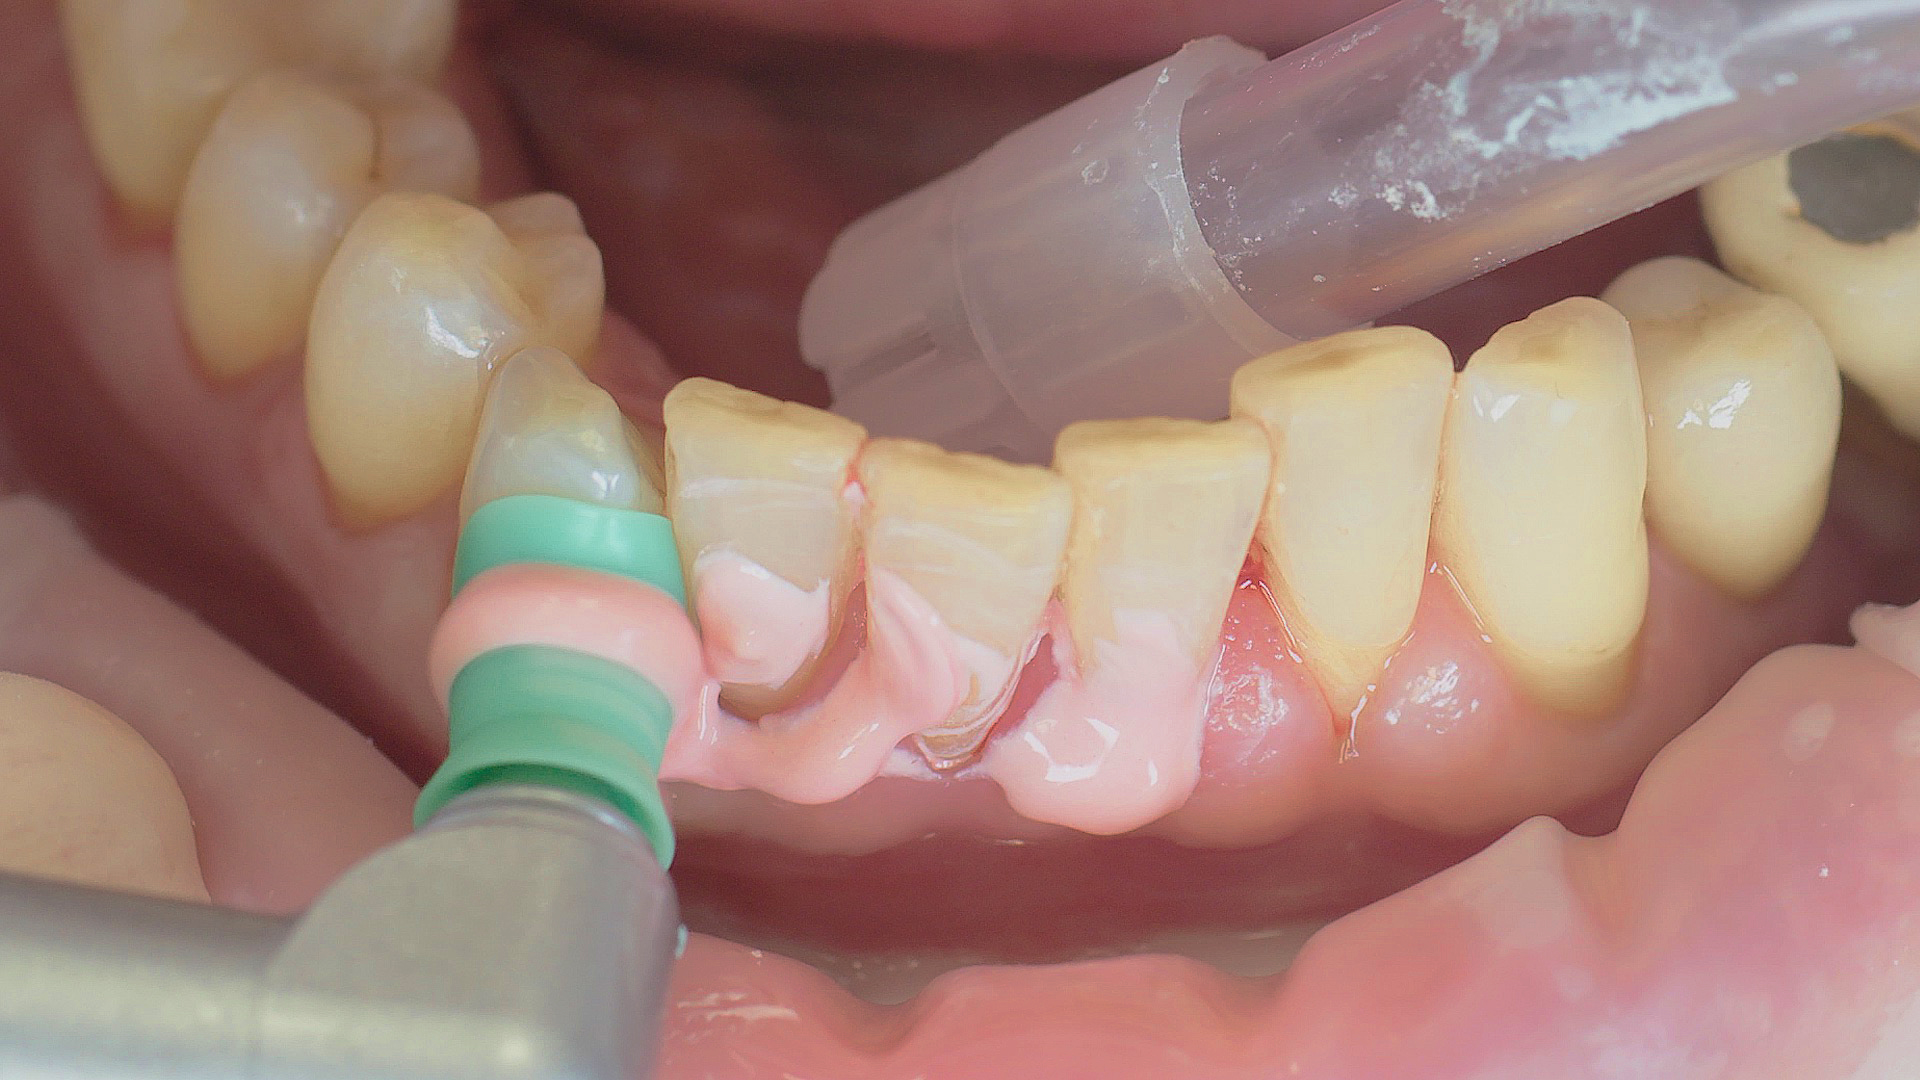

Every dental examination is based on a detailed medical history combined with targeted diagnostics con- taining as much detail as possible: The dentist records systemic risk factors such as diabetes or smoking and identifies any potential increased tendency to inflammation.[3] Hard and soft tissues are examined and periodontal pockets are probed in a screening test according to PSR (Periodontal Screening and Recording). In case of abnormal findings, the periodontal status is then re- corded and therapy is initiated where necessary. This treatment begins with professional biofilm management, by using, for example, rotary cups and polishing com pounds (Fig. 1), and comprehensive instructions in oral hygiene. Sonic or ultrasonic systems remain an effective alternative or supplement to manual instruments for sub- gingival debridement and biofilm management (presentation by Prof. Dr Ulrich Schlagenhauf;